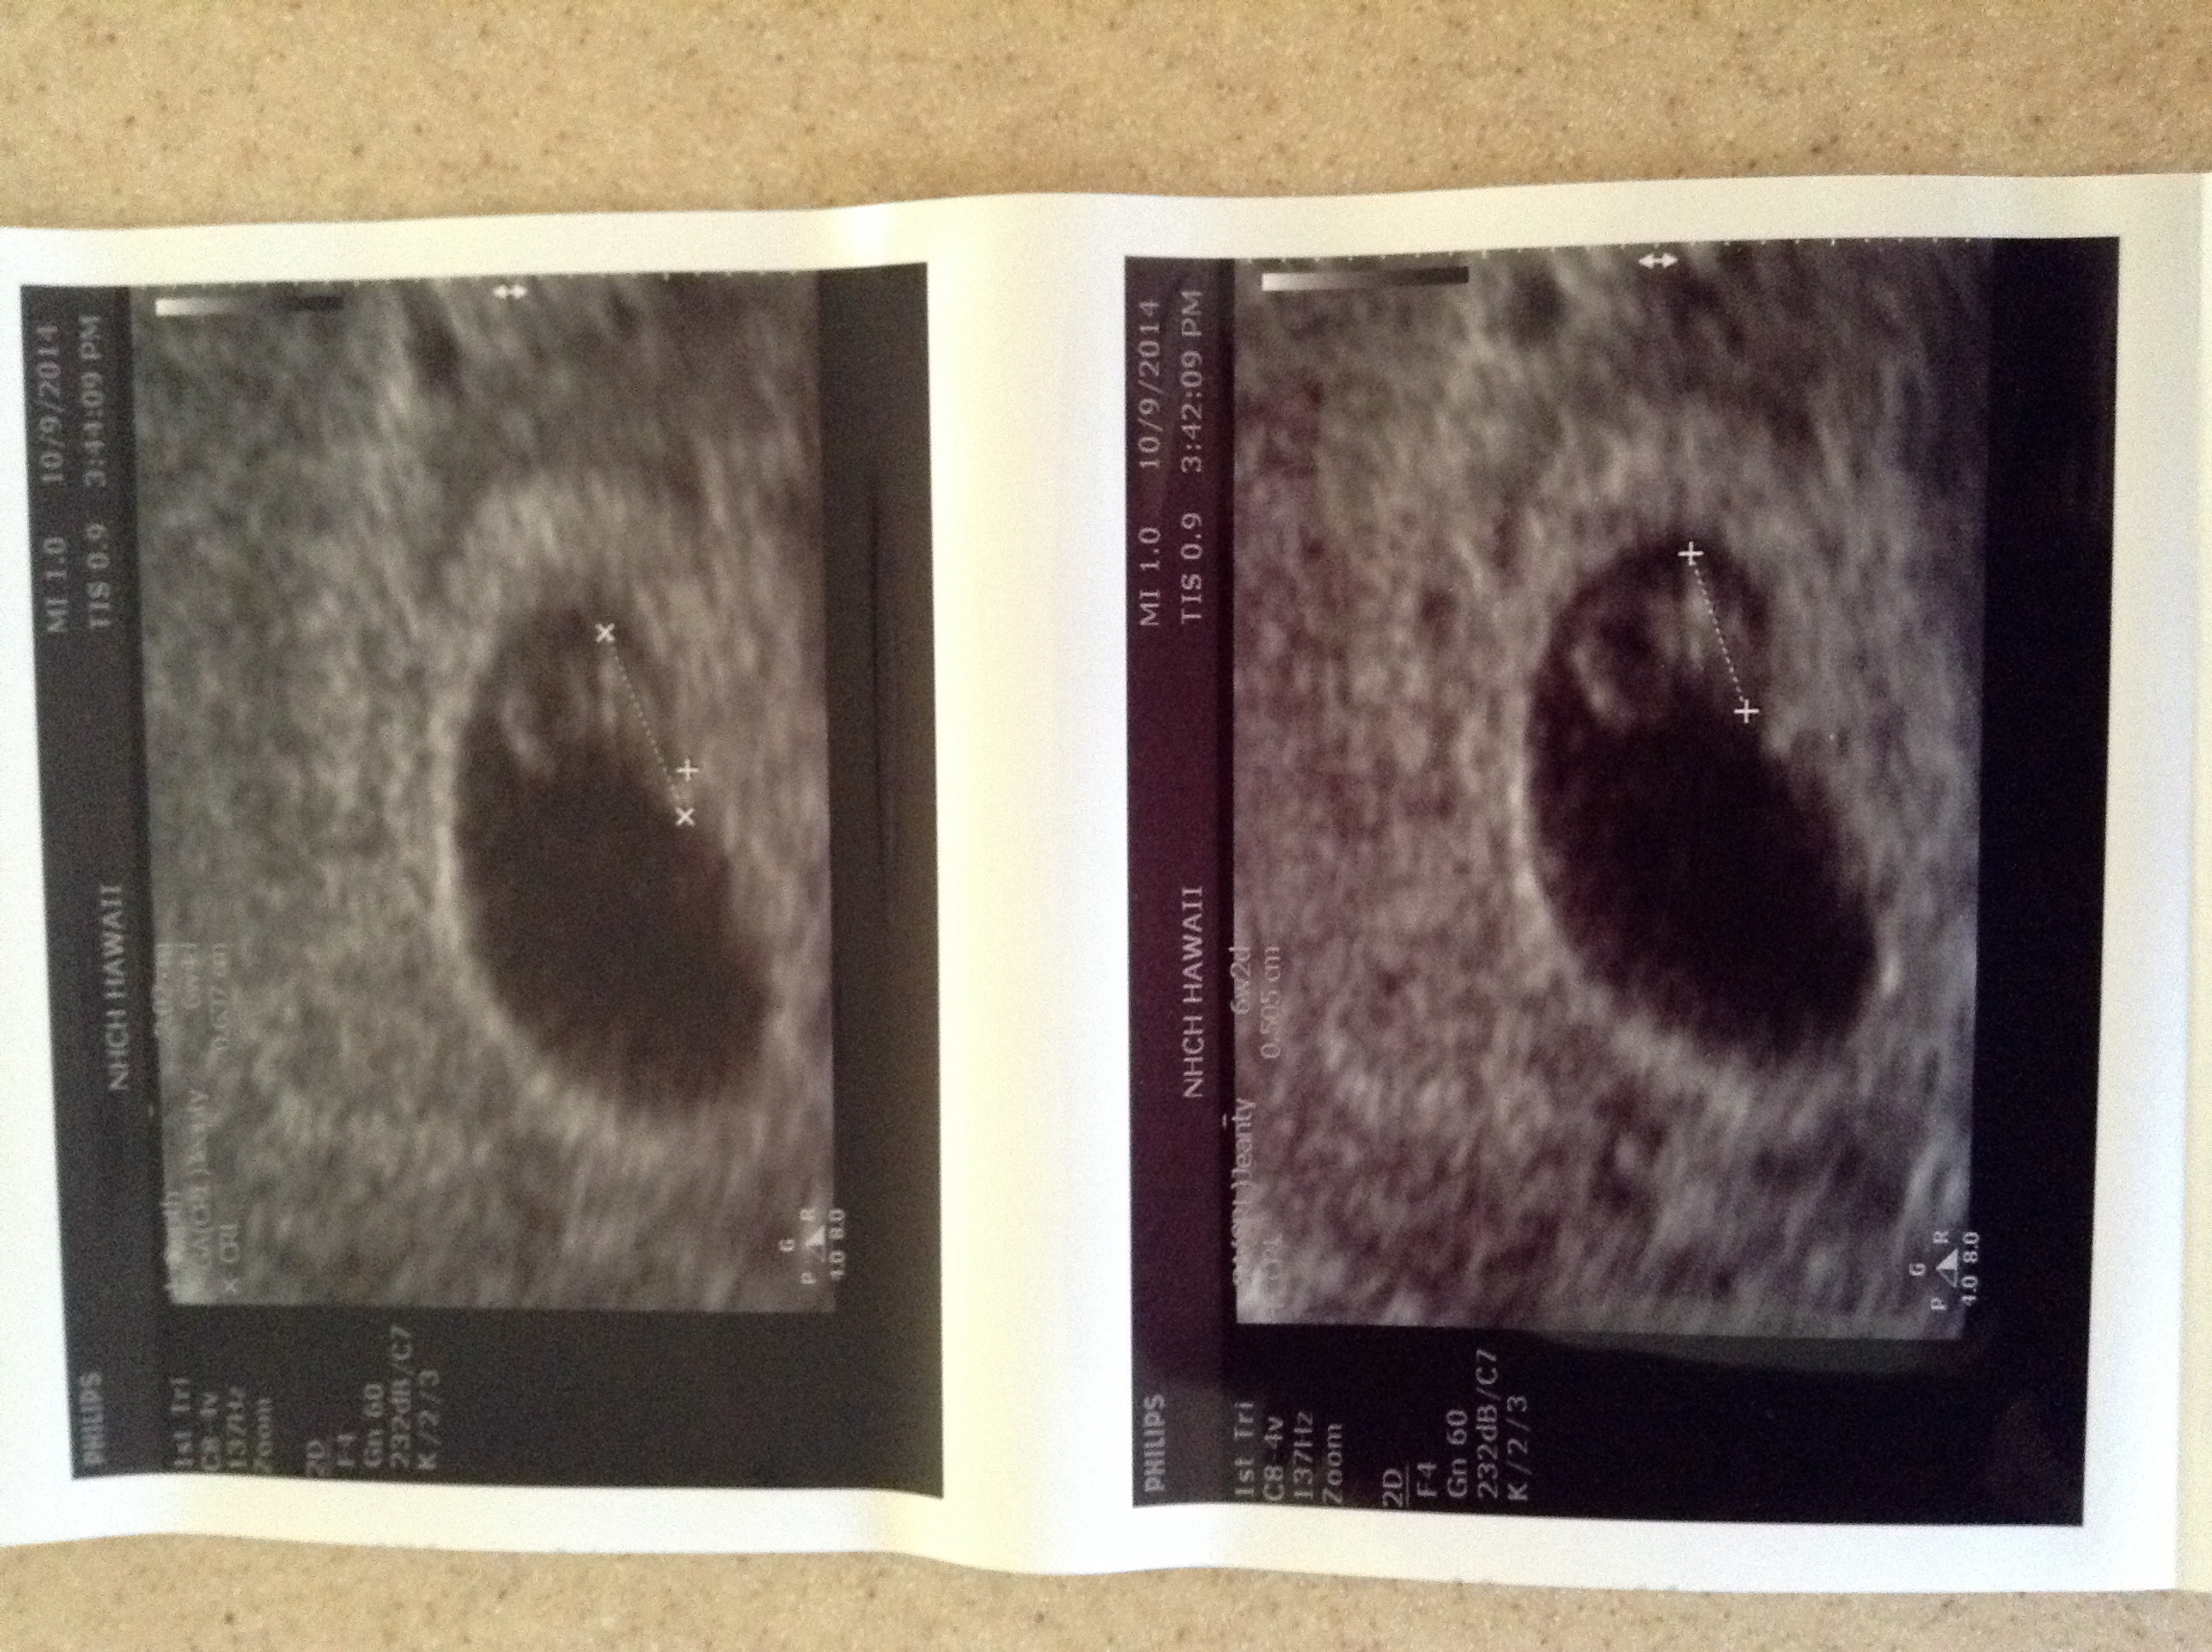

• Had my first yesterday, based off my lmp I'm 6w3d. We saw a fluttering heartbeat at a rate of 116/min, a gestational sac, and yolk sac, but based off us I'm 6w0d. I'm soo excited, my us looked like a little sparkling diamond ring in my uterus .. I'm nervous but excited too!! Next us in 4weeks